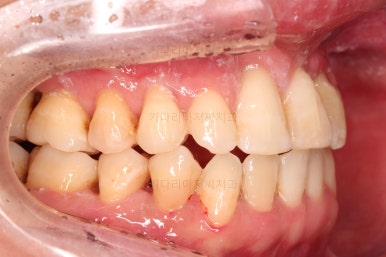

1. 초진 시 입안의 모습

부산구순구개열교정 키다리아저씨치과에 처음 내원하셨을 당시의 입안의 모습입니다.

이번 환자분도 이와 같은 일반적인 특징이 그대로 나타나 있었습니다.

양측성 구순구개열이었으므로 작은 앞니(대문니와 송곳니 사이)가 양쪽 다 결손이었고, 또 다른 이유로 아래 앞니도 1개 없는 상태였습니다.

초기 단계의 주안점은 아랫니와 악궁과 어울리는 윗니 악궁의 형태를 만들어 주는 것이고요.

악궁확장장치를 사용하지 않은만큼 철사의 형태를 잘 잡아가면서 악궁 형태를 개선시킵니다.

교정 10개월째인데, 악궁형태 많이 좋아졌고, 가지런한 느낌도 많이 좋아졌습니다.